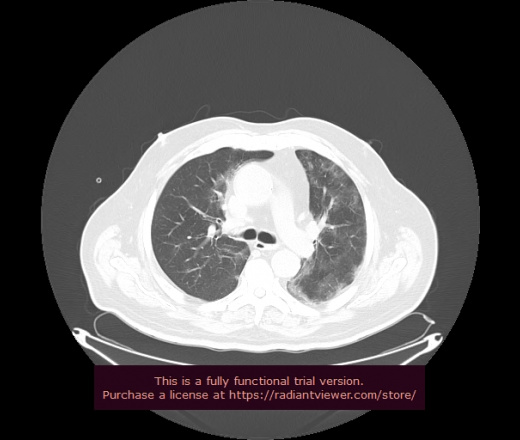

Уважаемые коллеги, если имеется интерес, сможете ли Вы спрогнозировать дальнейшее +-одинаковое течение процесса у 4 данных разных пациентов? Зацепиться где-то можно очень просто, где-то нельзя.